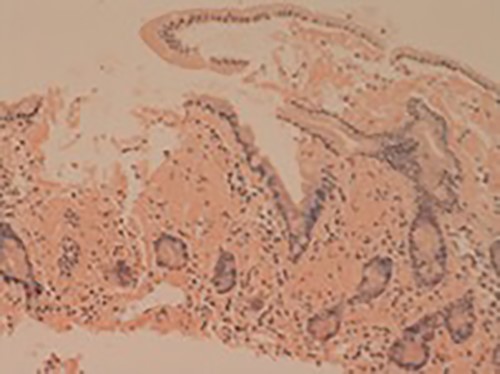

Her liver biochemistry continued to deteriorate so a transjugular liver biopsy was performed. Histology from both liver and duodenal biopsies was consistent with amyloidosis on Congo red staining (Figs 1 and 2, respectively). A subsequent bone marrow biopsy, organized by the haematologists, revealed a low level infiltrate of plasma cells consistent with multiple myeloma.

Small bowel mucosa (Congo red, x20): the substance is positive with Congo red stain in keeping with amyloid (salmon pink staining under standard light microscopy).